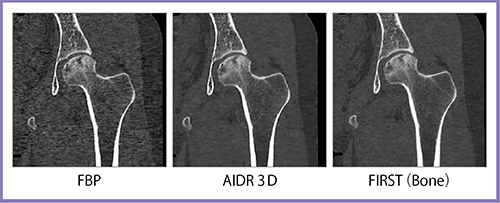

股関節CTは,FBPと比べるとAIDR 3Dでも大幅にノイズが低減されているが,FIRSTではさらにノイズが低減され,骨梁構造も描出できている(図7)。また,ストリークアーチファクトが強く出やすい肩口の頸椎CTでも,FIRSTではアーチファクトが抑制できている(図8)。

図7 股関節CT

図8 頸椎CT